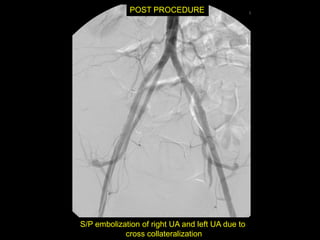

Angio after MRI

POST PROCEDURE

S/P embolization of right UA and left UA due to

cross collateralization

1 month follow up

HCG < 5 mIU/mL

No flow in area โ€“ smaller in size

Felt residual hematoma

Will continue US follow up

D&C complicated byPerforation, AVM w RPOC at Site of Perforation โ€ข AVM โ€“ Acquired or Congenital โ€ข Acquired โ€“ Traumatic โ€“ D&C, TAB, uterine surgery โ€“ Less common: Endometrial / Cervical CA, GTD โ€“ Clue on US: numerous tortuous vessels, high velocities โ€ข Tx: โ€“ transcatheter arterial embolization โ€ข Potential to preserve fertility โ€“ UA ligation, hysterectomy

POST PROCEDURE S/P embolizationof right UA and left UA due to cross collateralization

1 month followup HCG < 5 mIU/mL No flow in area โ€“ smaller in size Felt residual hematoma Will continue US follow up